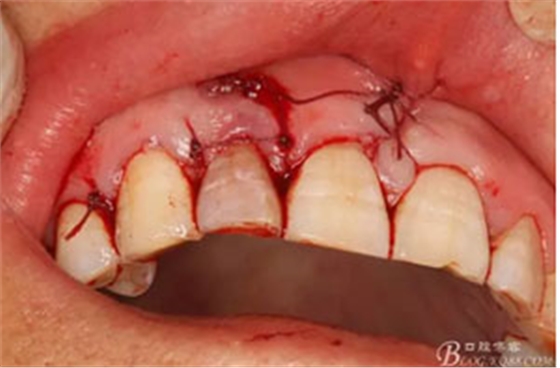

圖6.行唇側(cè)角形切口(11近中垂直切口+齦溝內(nèi)水平切口)垂直切口距離前庭溝約1~2mm。這樣可以減輕術(shù)后腫脹。

圖7. 角形切口中的齦溝內(nèi)切口情況:11號刀片伸進(jìn)齦溝內(nèi)斜切。

圖20.間斷縫合。